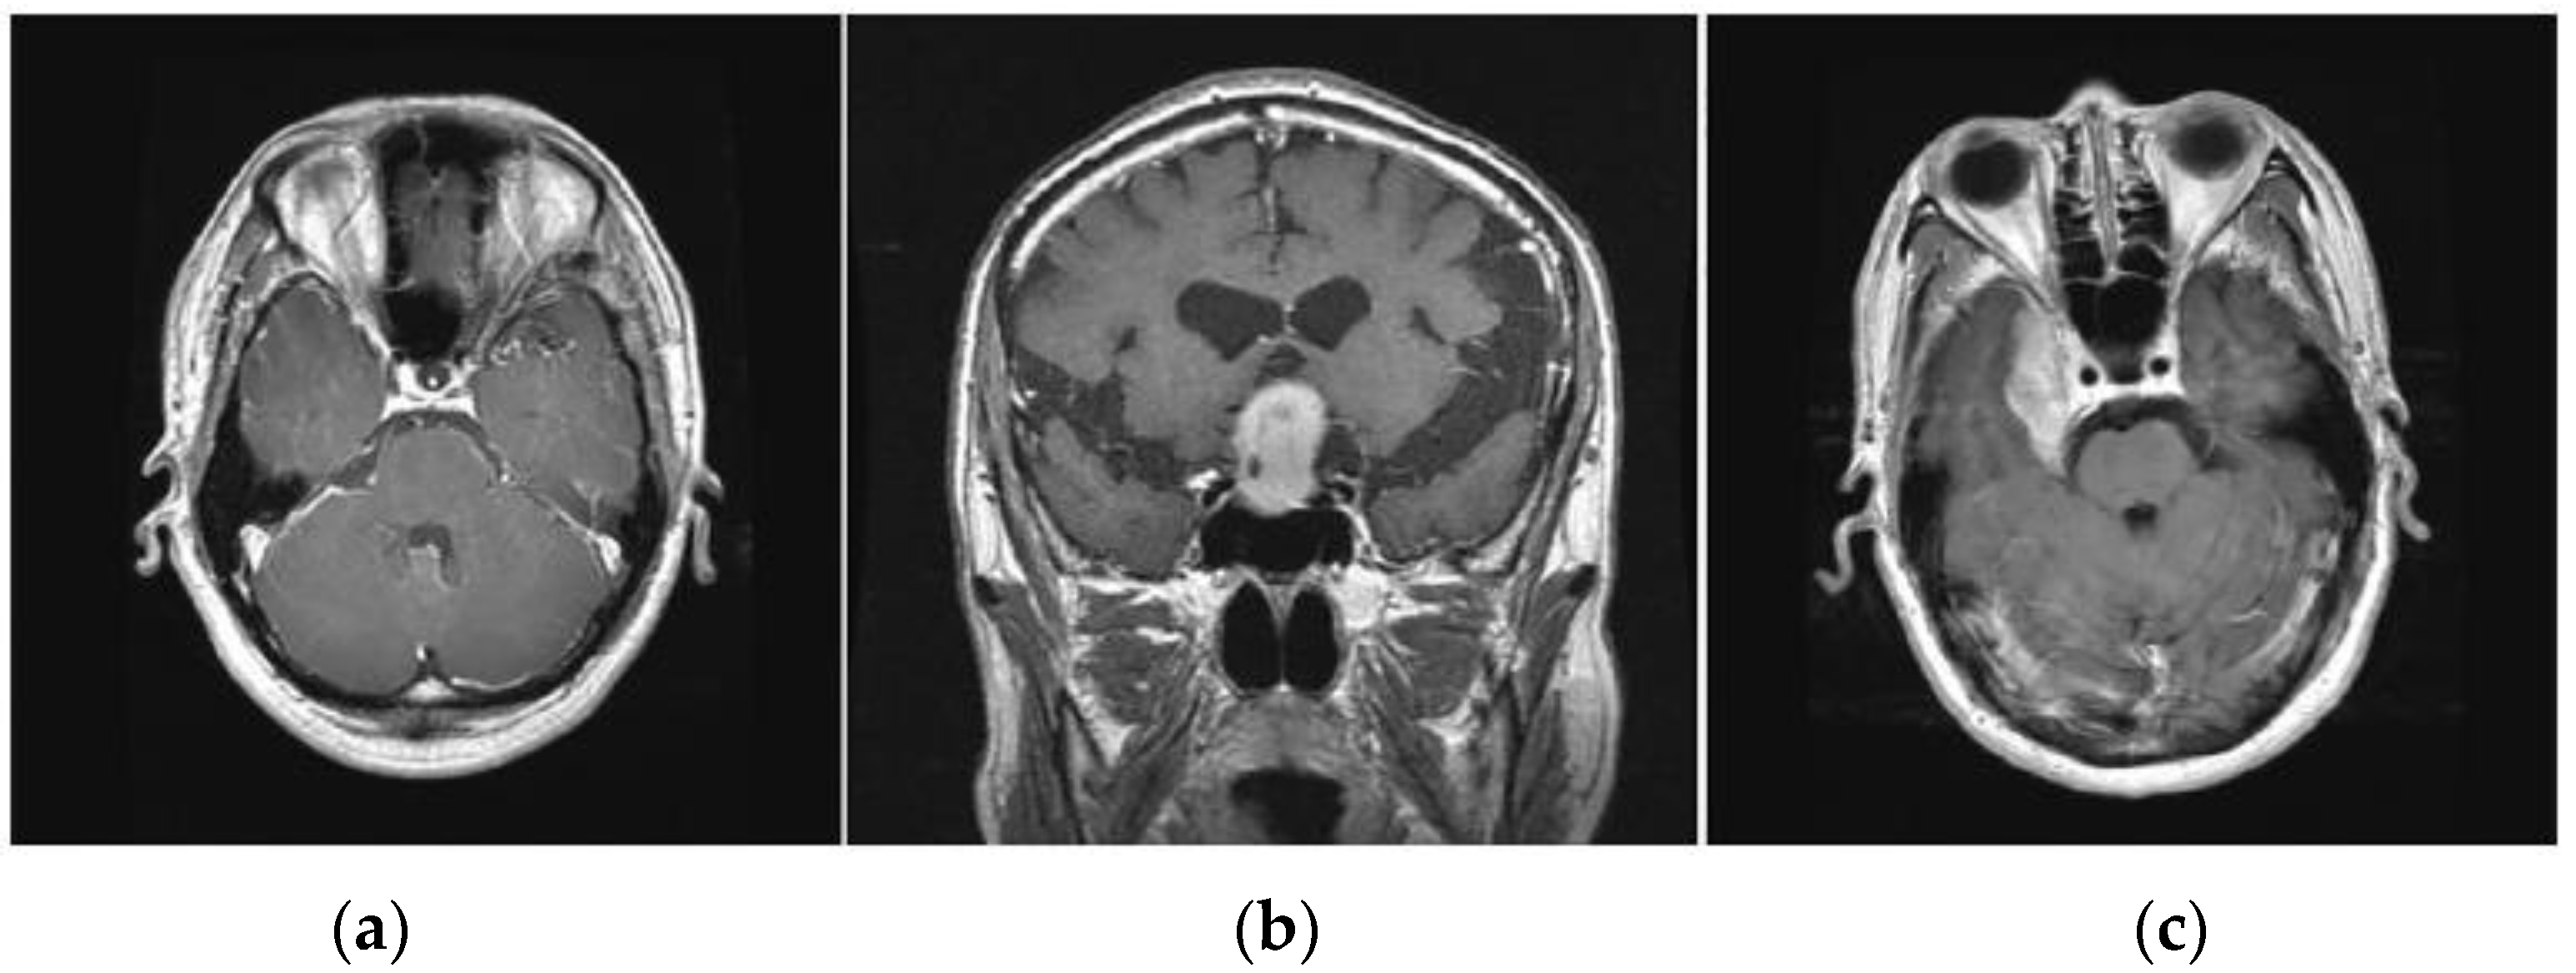

| Kind of Tumor | Types of Planes | Number of Images | Total Images | Training Data (60%) | Validation Data (20%) | Testing Data (20%) |

|---|---|---|---|---|---|---|

| Glioma | Sagittal | 495 | 1426 | 855 | 285 | 286 |

| Coronal | 437 | |||||

| Axial | 494 | |||||

| Meningioma | Sagittal | 231 | 708 | 424 | 142 | 142 |

| Coronal | 268 | |||||

| Axial | 209 | |||||

| Pituitary | Sagittal | 320 | 930 | 558 | 186 | 186 |

| Coronal | 319 | |||||

| Axial | 291 |